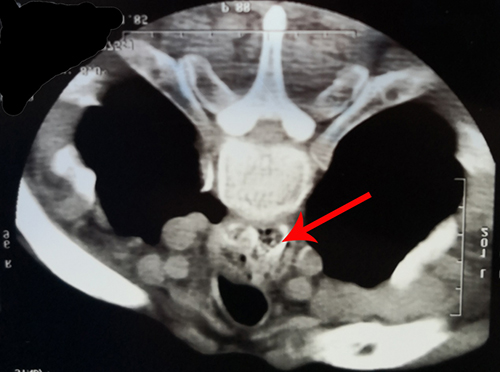

食管异物是医院消化内科常见急症,多以枣核、鱼刺为主。患者男性、65岁,近期患有脑梗塞,误食鸡骨后即感进食困难,在当地县医院行CT提示食管骨性异物。

箭头所示为异物